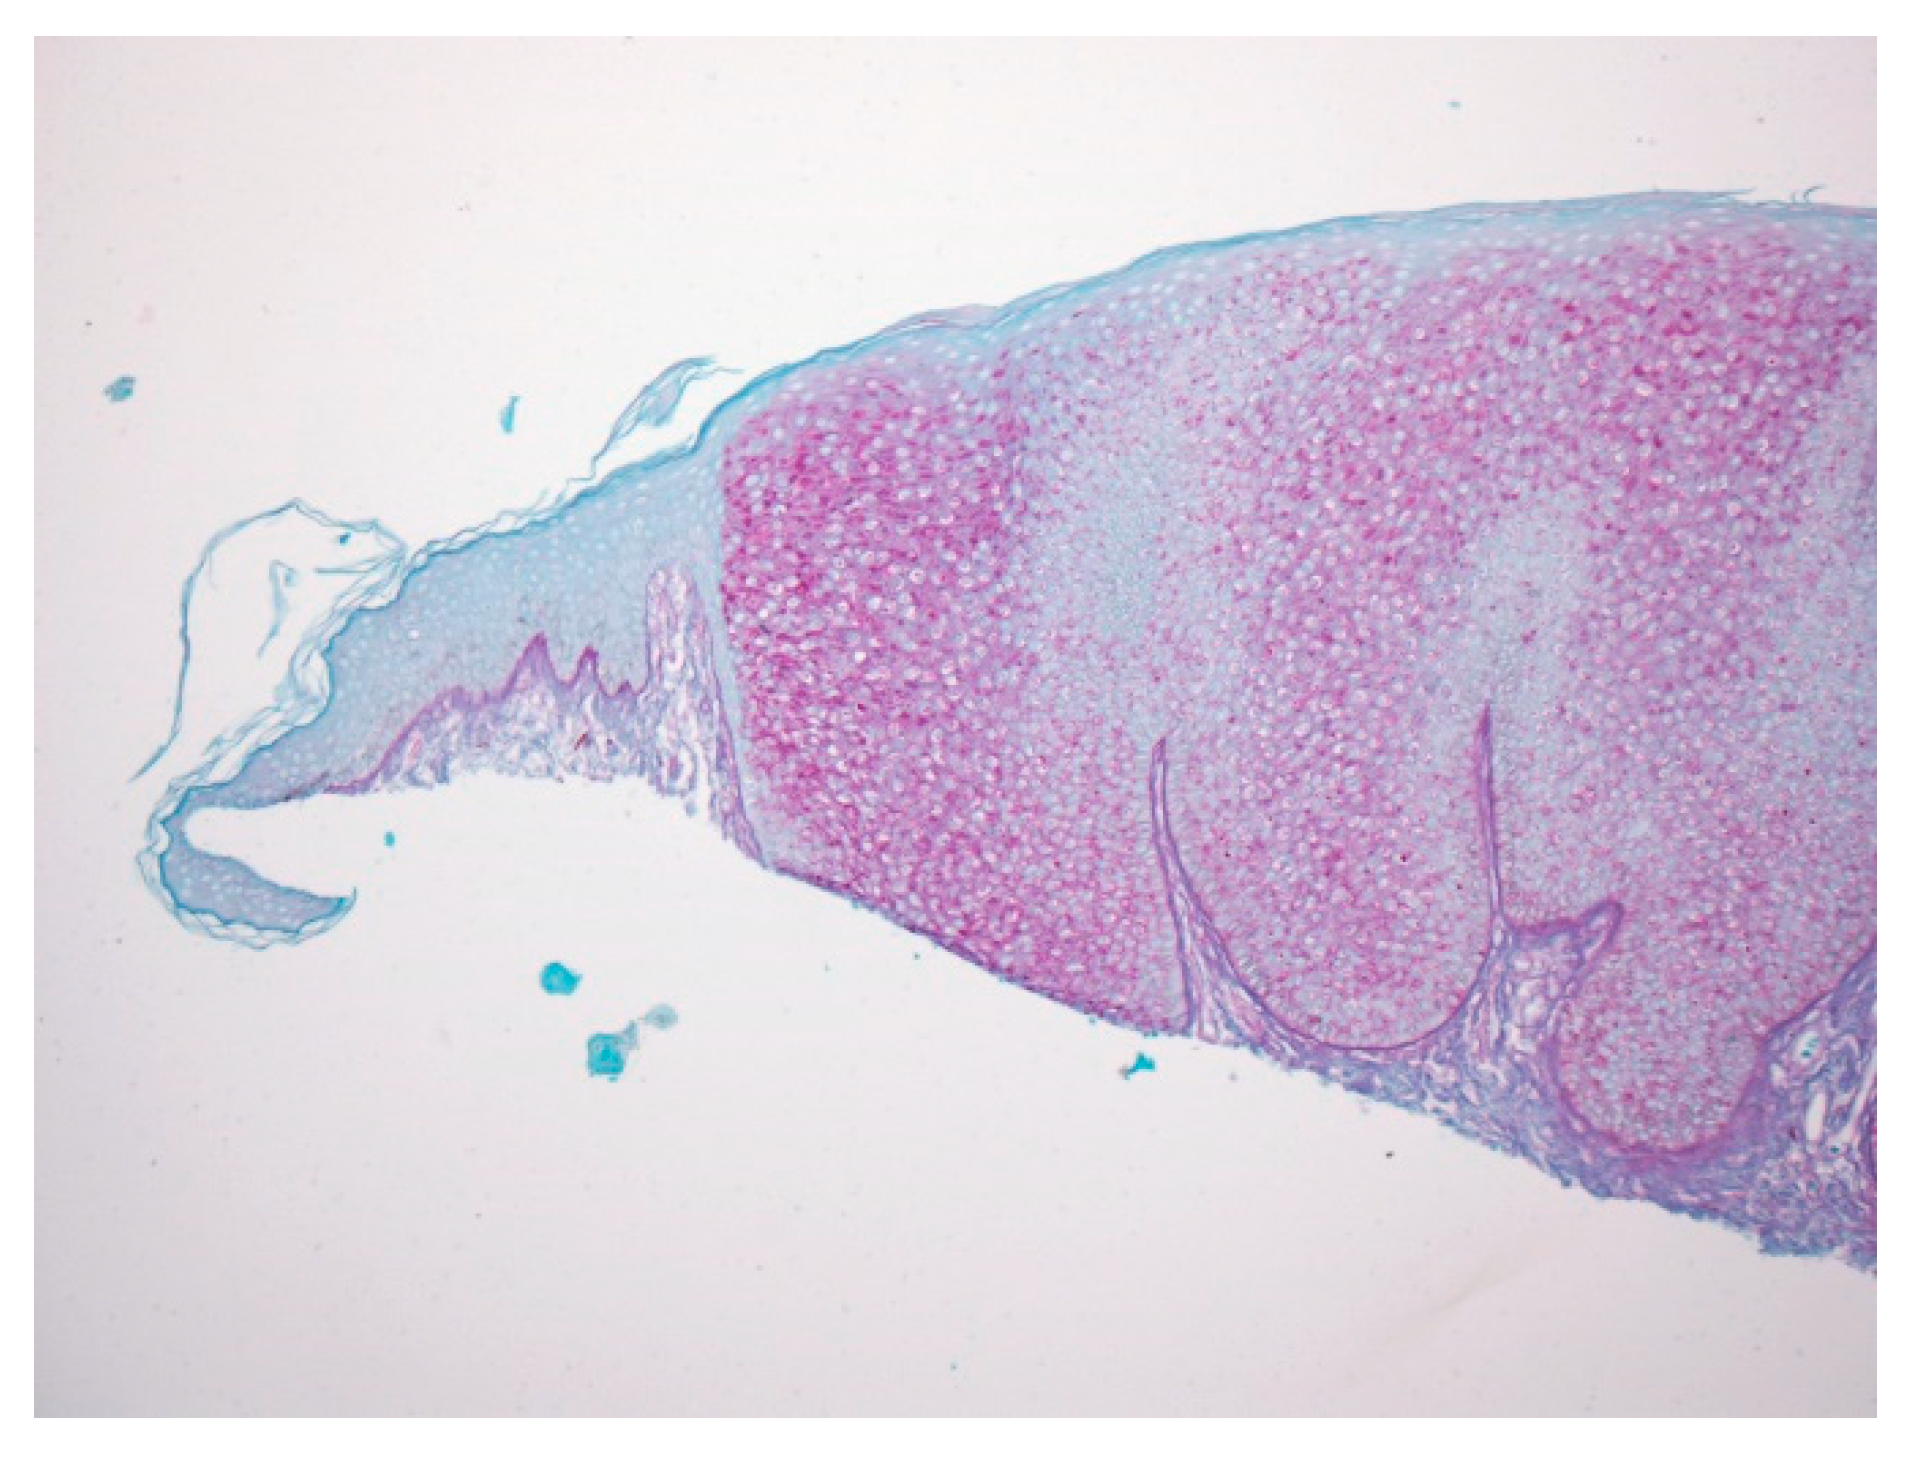

Figure 3.

With PAS staining, the lesion is sharply demarcated from the normal epidermis, suggesting glycogen accumulation in lesional keratinocytes.

Figure 4.

The cytoplasm highlighted by the PAS stain is negative after diastase treatment, confirming glycogen accumulation.